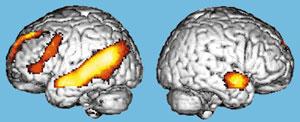

Очень важна проблема мозгового обеспечения внимания у человека. Ею в нашем институте занимается и моя лаборатория, и лаборатория Ю.Д.Кропотова. Исследования ведутся совместно с коллективом ученых под руководством финского профессора Р.Наатанена, который открыл электрофизиологические корреляты так называемого механизма непроизвольного внимания. Чтобы понять, о чем идет речь, представьте ситуацию: охотник крадется по лесу, выслеживая добычу. Но он и сам является добычей для хищного зверя, которого не замечает, потому что настроен только на поиск оленя или зайца. И вдруг случайный треск в кустах, может быть, и не очень заметный среди птичьего щебета и шума ручья, мгновенно переключает его внимание, подает сигнал: “рядом опасность”. Механизм непроизвольного внимания сформировался у человека в глубокой древности как охранный механизм, но работает и сейчас: например, человек ведет машину, слушает радио, слышит крики детей, играющих на улице, воспринимает все звуки окружающего мира, внимание его рассеянно, и вдруг тихий стук мотора мгновенно переключает его внимание на машину - он осознает, что с двигателем что-то не в порядке (кстати, это принципиально схожее с детектором ошибок явление). Такой переключатель внимания работает у каждого человека. Нами обнаружены ПЭТ корелляты этого механизма, а Ю.Д.Кропотовым - электрофизиологические корелляты у больных с имплантированными электродами. Смешное. Мы закончили эту работу перед очень важным и престижным симпозиумом. В спешке. Поехали туда, и там, где у нас двоих были доклады, мы с удивлением и «чувством глубокого удовлетворения» неожиданно заметили, что активация в одних и тех же зонах. Да, иногда двоим сидящим рядом надо поехать в другую страну, чтобы поговорить.

Активации первичной слуховой коры. Активации префронтальной коры. ПЭТ корреляты феномена негативности рассогласования (отражение первичной автоматической обработки слуховых стимулов). |

Что же мы получили? Исследованы ПЭТ корреляты неосознанного внимания, т.н. феномена негативности рассогласования - непроизвольное переключение внимания к девиантным акустическим стимулам. Проведены иследования негативности рассогласования при предъявлении как простых слуховых стимулов (тонов), так и более сложных: аккордов и фонем. При всех этих видах стимулов обнаружены сходные корреляты негативности рассогласования. Первый паттерн активаций расположен в верхневисочных отделах (слуховой коре) обоих полушарий, что указывает на реакцию на изменение тональности, даже незначительную, причем более выраженная активация височной коры имеет место, когда девиантные стимулы перемешаны со стандартными, чем при предъявлении только девиантных стимулов. Более выраженная активация присутствовала в правом полушарии, что соотвествует предшествующим электрофизиологическим данным. Второй паттерн - активации лобной доли, причем они присутствовали как при стимуляции только девиантными, так при сочетании стандартных и девиантных стимулов. В лобной доле имелись фокусы префронтальной активации, что тоже соотвествует предшествующим электрофизиологическим данным, а также в области средней и верхней лобной извилин. Также отмечались активации передних отделов поясной извилины и билатеральные активации задних теменных областей (правосторонняя теменная активация была описана при магнитоэнцефалографии). Активации лобной доли, скорее всего, лежат в основе сознательной уверенности субъекта в изменении стимула, который уже был неосознанно выделен слуховой корой обоих полушарий. Такая роль лобной доли как структуры, обеспечивающей переключение внимания, подтверждается выраженными паттернами активаций, которые вызываются девиантными тонами, когда их предъявляют в чистом виде с относительно длинными, нерегулярными интервалами, что известно из предыдущих исследований. Активации передних отделов поясной извилины и теменной коры могут включаться в мозговые механизмы переключения внимания. Дополнительно была выявлена активация коры островка Рейли, что не было известно по предыдущим электро- и магнитоэнцефалографическим исследованиям, но подобные активации были получены и по результатам прямой регистрации через вживленные электроды вызванных потенциалов с этих структур в лаборатории программирования действий ИМЧ РАН. Роль этой структуры в обеспечении процессов внимания в настоящее время неизвестна и подлежит дальнейшему изучению. Таким образом, были выявлены паттерны мозговых активаций, проливающие свет на механизмы, с помощью которых девиантные слуховые стимулы вызывают непроизвольное переключение внимания.

Кроме непроизвольного внимания есть еще и селективное. Так называемое внимание на коктейль приеме. Все говорят разом, а вы следите только за собеседником, подавляя неинтересную вам болтовню соседа справа. Похожая ситуация изображена на рисунке. В оба уха расказывают истории. Разные. В первом случае следим за историей в правом ухе, а во втром - в левом. Видно, как меняется активация областей мозга. Заметим, кстати, что активация на историю в правое ухо значительно меньше. Почему? А потому, что большинство людей берут телефон в правую руку и прикладывают его к правому уху. Поэтому следить за историей в правом ухе проще.

Латерализация мозгового обеспечения селективного внимания. Слева внимание на левое ухо, справа естественно на правое. Видно, что активированы различные зоны. |

Сравнение слухового и зрительного селективного внимания. В задании на левостороннее слуховое селективное внимание по сравнению со зрительным вниманием при дихотическом прослушивании и одновременном зрительном предъявлении различных текстов также определяется активация слуховой коры противоположного полушария, что, как и на предыдущем рисунке, отражает селективную настройку слуховой коры, не зависящую от вида и сложности предъявляемых стимулов. Процесс же подавления обработки иррелевантных, но значимых зрительных стимулов при слуховом внимании вызывает выраженные активации зрительной коры (затылок). |

Показано, что слуховое селективное внимание при бинауральной стимуляции избирательно активирует области височной коры, специфичные для слухового предъявления сигналов. Эти результаты согласуются с мировыми данными, подтверждая, что и степень выраженности этой полушарной латерализации также зависит от направления внимания. Наши данные указывают, что этот эффект латерализации (односторонности) сконцентрирован в первичной слуховой коре, причем селективное внимание к латерализованным звукам усиливает активность слуховой коры преимущественно в первичных слуховых зонах контрлатерально направлению подачи стимулов. То есть слуховая кора селективно настраивается в соответствии с направлением внимания, что обычно не определяется при экстракраниальной регистрации электрической или магнитной активности мозга. Наиболее вероятно, что имеющая место полушарная латерализация активации слуховой коры, ассоциирующаяся с пространственно сфокусированным слуховым вниманием, вызвана подготовительной настройкой на внимание левой и правой слуховой коры в соотвествии с направлением внимания, предшествующей предъявлению стимулов и происходящей при фокусировке пространственого внимания. Префронтальная кора представляется вовлеченной в контроль за вниманием, т.к. в ряде работ в ней было выявлено усиление локального мозгового кровотока и усиление электрической активности. В наших исследованиях усиление префронтальной активности, особенно в ее дорзолатеральном отделе, ассоциируется с контролем настройки внимания правой и левой слуховой коры, причем большая выраженность активаций в лобной области при слуховом по сравнению со зрительным селективным вниманием вызвана, скорее всего, большим когнитивным усилием для выполнения слуховой дискриминации, когда внимание должно было быть направлено на один из двух конкурирующих потоков стимулов, тогда как выполнение задания на зрительное внимание не требовало внутримодального селективного внимания. Таким образом, было показано: слуховая кора селективно настраивается в соотвествии с направлением внимания. Эта настройка контролируется префронтальным исполнительным механизмом, что проявляется усилением префронтальной активности при слуховом селективном внимании.